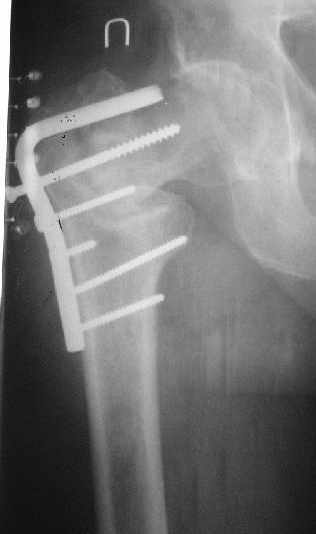

Как предлагали уважаемые коллеги, сегодня наложили спице-стержневой дистрактор таз-бедро, перед этим попробовали закрытую остеоклазию под в/в анестезией, движение в т/б суставе ( или в ложном суставе! ) восстановлен.

Р-снимки сразу п/о, следующий после дистракции, аксиальная - прощу извинения за плохое качество снимков.

Мне кажется надо еще продолжать постепенную дистракцию. И еще которая наверху шейки по моему это осколок от шейки, и она фиксирована оссификатом надвертлужной обл. Поэтому при повторной операции видимо придется открыто мобилизовать т/б сустав.